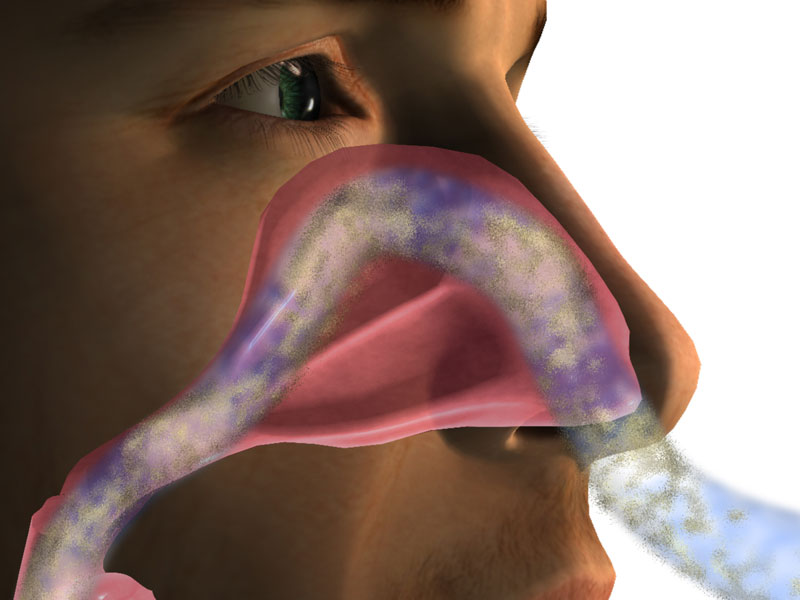

The objective of the study was to quantify the effects ambient relative humidity has on the mucociliary flow rate of the human nose.

Ewert developed a new in vivo technique, using a stereo-microscope for direct observation of dyed sub-micron powder tracers (calcium phosphate) placed inside subjects' nostrils. The stereo-microscope enabled a magnified and perfectly illuminated visibility of moving tracers on the nasal septum of subjects. The observed subjects were laying on their back, breathing room air (temperature 23 ±2°C, relative humidity 20 to 88%RH, depending on season, mean RH 43.55%).

The data showed a continuous decrease (linear regression) in mucociliary flow rate below 70%RH. As the air became drier, mucociliary clearance slowed.

A steady difference in mucous velocity between the so called “slow side” and “fast side” confirmed the known phenomenon of “nasal cycle” (mucociliary flow velocity and air flow alternately increase and decrease, induced by congestion and decongestion of nasal mucosa).